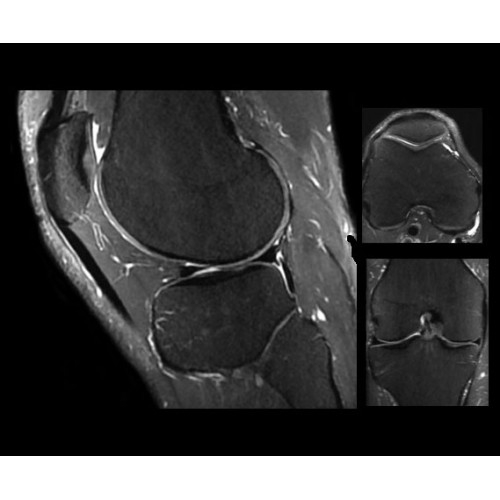

Система SIGNA PET/MR предлагает впечатляющие клинические возможности и открывает доступ к наиболее полным пакетам программных приложений.

Стандартный пакет приложений SIGNA Works позволит вам достичь желаемых результатов в клинической практике благодаря набору высокоэффективных средств визуализации. Программные приложения, входящие в состав данных клинических пакетов, включают широкий спектр контрастов, функции обработки 2D- и 3D-данных, а также возможность коррекции артефактов движения. SIGNA Works предоставляет набор инструментов, необходимых для проведения эффективного клинического исследования.